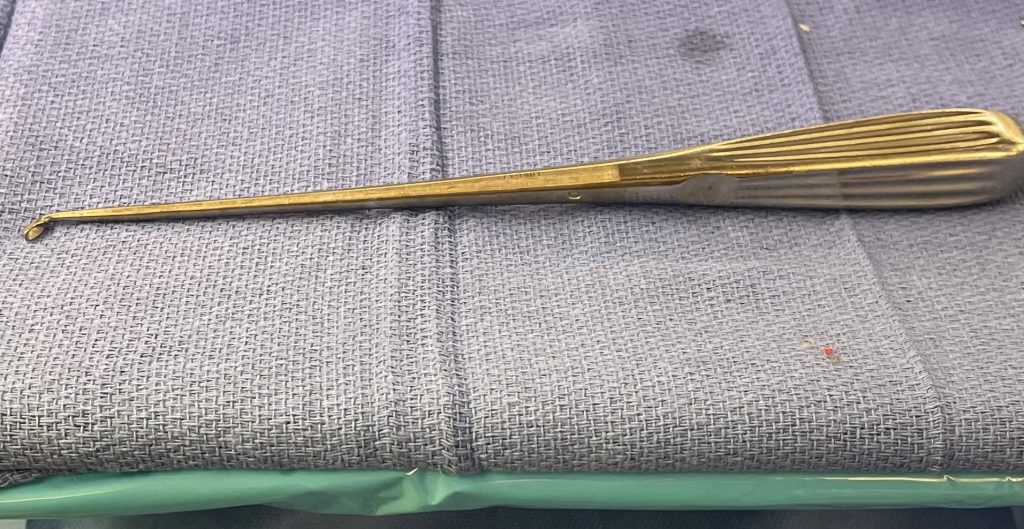

Fig 1: Upbiting curette

Revision lumbar spine surgery is amongst the most difficult of surgeries, not just in spine surgery, but of all categories of surgery. I don’t believe many spine surgeons will argue with this fact. The placement of hardware is getting slicker and easier, but there is no modern computerized technology that will improve upon the ability to separate and pick away scar tissue to establish dural planes in order to successfully decompress a patient who has redeveloped stenosis after a prior laminectomy and fusion. It does in fact take time and experience to understand what you can and can’t get away with, with regards to pressure, tension, aggressiveness of separation of planes during a dissection, and how to use the necessary tools to your advantage. A very important tool is the upbiting curette (Fig 1), which allows bone to be separated from soft material like scarred dura. This requires a very close hugging action to the undersurface of the bone of the lateral recess; if you get comfortable you can sweep an opening plane between the bone and dura since the back edge of the curette is smooth. It is important to identify opportunities of separation of planes and being patient to tend to a certain region first in order to gain the necessary plane to help you tackle another region that would have been difficult from an initial approach.